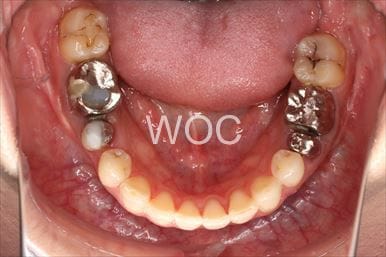

治療前1

- 年齢:20歳女性

- 主訴:出っ歯が気になる

- 基本矯正料金:120万円

- 治療期間:1年7ヶ月

- 抜歯部位:上顎両側第一小臼歯